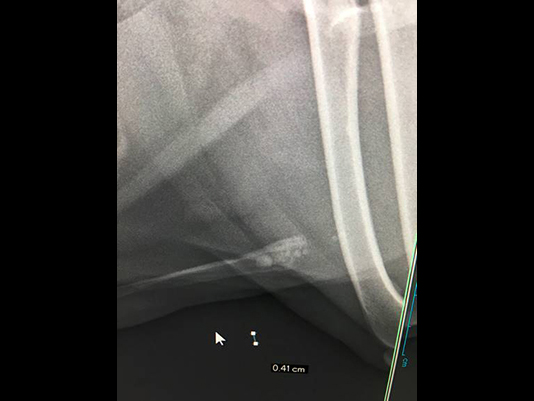

尿道結石がスタックされていて膀胱内に押し込むこともできない。押し込んでも何度も落ちてきて尿道に詰まってしまうことがある。

尖っている結石が粘膜に刺さっていると押し込むことも不可能になります。

他院からの紹介:結石が詰まってチョロチョロしか尿が でずカテーテルも通らない。

結石破砕を依頼された。左が破砕前、陰茎骨に結石が詰まっている。

右は破砕後。破砕が可能だったので尿道切開をせずに2時間後に帰宅した。